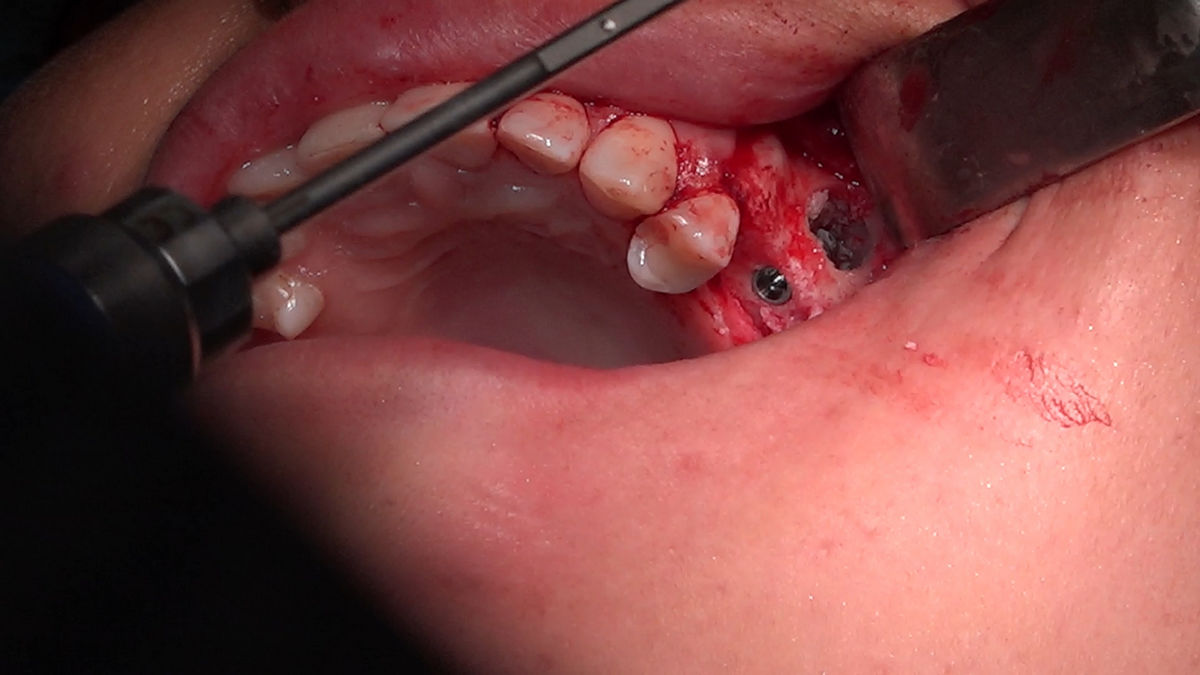

Chirurgia implantologiczna to temat wiodący 5 Sesji X Sezonu Practiculum Implantologii, która się odbyła 23-24 października 2020 roku. Bierze w nim udział 16 adeptów implantologii stomatologicznej. Zabiegi z udziałem Pacjentów jak zwykle poprzedziło omówienie i planowanie, tym bardziej, że zgodnie z planem wykonana została implantacja z wykorzystaniem szablonu chirurgicznego, który przygotowało laboratorium dentystyczne Wiligała Lab. Kursanci wykonywali szereg zabiegów implantologicznych i chirurgicznych oraz regeneracyjnych z zastosowaniem PRF, w tym sinus lift. Przeprowadzali je pod kierunkiem Lidera Umiejętności Implantologicznych dr n.med. Violetty Szycik, która wysoko oceniła wykonanie zabiegów.